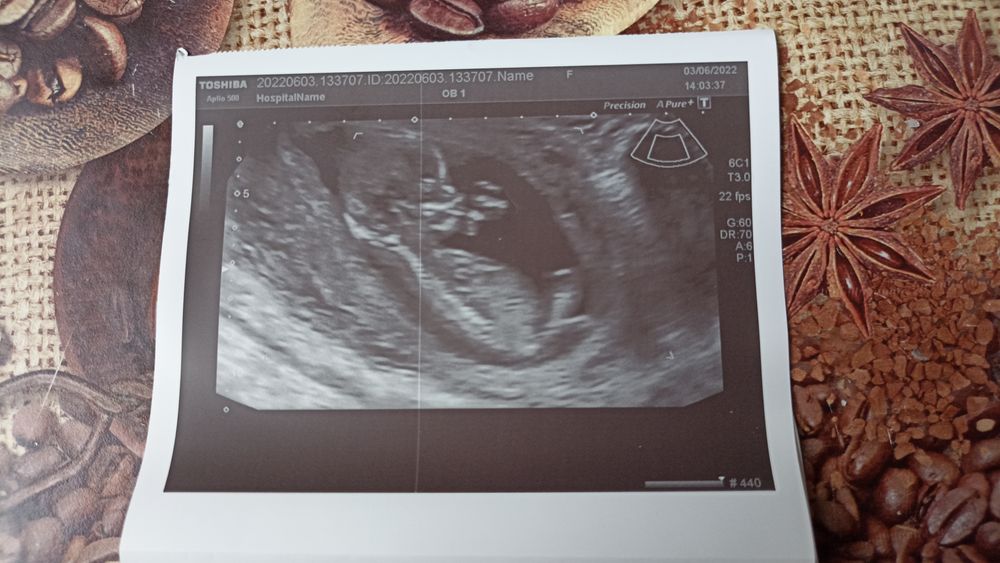

Девочки вот до я понимаю узист 4 фотки даже видео дал снять! Мой малыш с прошлого УЗИ вырос на 4 мм ❤❤❤🤗😊